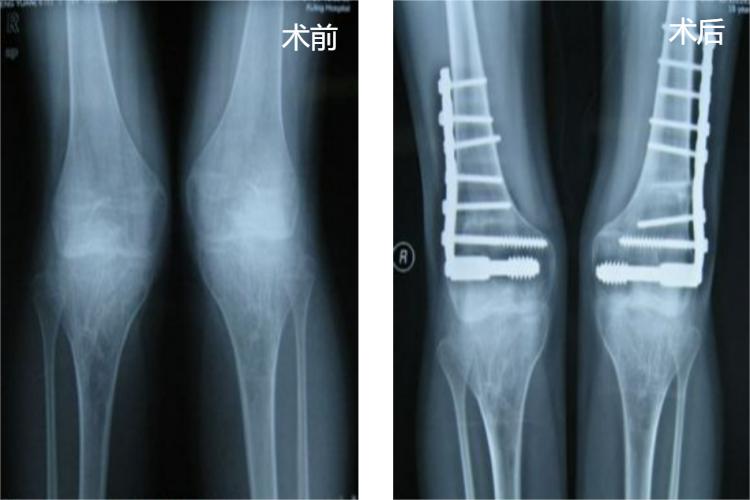

X型腿畸形矫正术应根据畸形发生的部位选择在股骨远端或胫骨近端进行。多数做股骨髁上截骨矫形术。术前应根据X线片明确矫正度数,并注意保留10度左右的生理外翻角,术后长腿管形石膏固定6-8周。

X型腿矫正术后需要免负重1个月,第2-3个月可以部分负重,3个月后一般才可完全负重。而且因手术不进入关节,所以不需要进行膝关节的屈伸活动练习,术后1年左右即可拆除钢板。